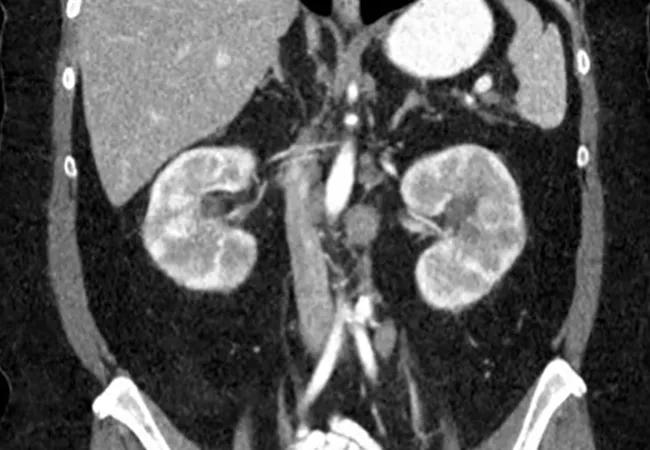

CT imaging was obtained, revealing a potentially infiltrative pathology and enlarged cervical, mediastinal and retroperitoneal lymph nodes, including multiple bilateral renal masses with abnormal markings.

Following treatment, the patient’s CT scan (left) showed resolution of masses, and the PET scan (right) did not pick up any significant hypermetabolic lesions in the kidneys.